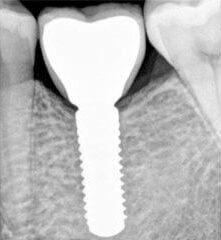

Probleem. Eemaldatud piimahammas.

Lahendus. Pärast 3 kuu möödumist, kui luu on paranenud, paigaldatakse hambaimplantaat ja kinnitatakse kohe igemeformeerija.

Pärast 2,5 kuu möödumist paigaldati pärast implantaadi kinnitumist püsikroon.